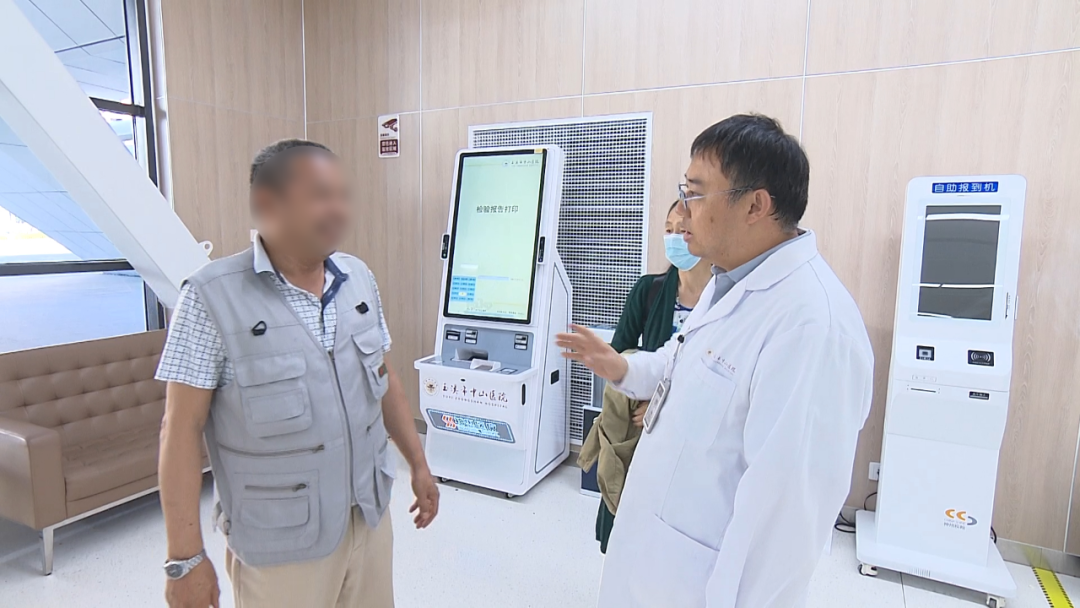

待罗先生术后出院康复稳定一段时间后,医院对罗先生进行术后回访和复查。罗先生兴奋地告诉医生:“之前以为要偏瘫了,是中山医院又让我恢复过来。你看我现在说话清晰,走路稳健,甚至开车也毫无问题,治疗效果非常好!”

经过超声复查,结果显示其血管恢复良好。罗先生和家人拿着良好的复查结果,对玉溪市中山医院的救治过程赞不绝口:“整个治疗过程中,医院对我的病情很重视很关心。我在‘家门口’就得到这么高水平、及时的医疗服务,治疗费用也比去大城市医院低很多,大大减轻了我们的经济负担。要是没有医院的及时救治,后果简直不堪设想!”